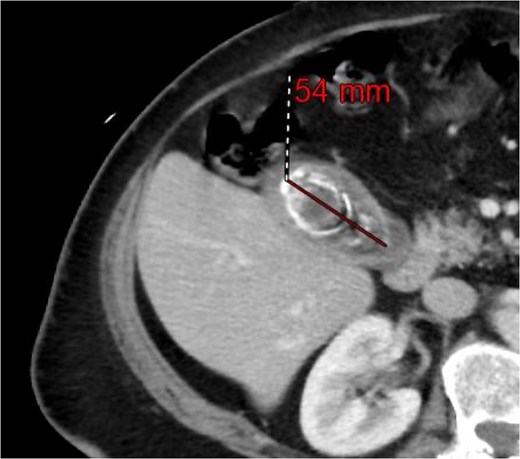

A 63-year-old obese female, known to have hypertension and diabetes, was admitted electively for laparoscopic cholecystectomy and laparoscopic incisional hernia repair with mesh. Prior to surgery, the enhanced computed tomography scan revealed a fat- containing supraumbilical hernia measuring 1.5 cm, a 54 mm gallbladder stone, and unremarkable liver pancreas, spleen, kidneys, and pelvis organs, with no evidence of intra-abdominal free air or fluid (Figs 1 and 2). The patient underwent surgery under general anesthetic using standard sterile procedures. We began with a supraumbilical incision ⁓3 cm above the umbilicus over the previous hernial site. After making a 1 cm longitudinal incision, we identified and opened the fascia, introducing a 12 mm port without immediate complications. The camera was inserted, gas was insufflated, and the abdomen was explored, revealing no immediate injury. An additional 11 mm port was inserted in the left upper quadrant for further exploration. Severe adhesions of the small bowel to the abdominal wall were noted. The first port was examined, and no bowel injury was found. LigaSure was utilized for adhesiolysis, followed by the insertion of two 5 mm ports in the right upper and lower quadrants, and a 5 mm port in the epigastric area. Laparoscopic adhesiolysis was performed, releasing the adhesions without bowel injury. The gallbladder, severely adhered to the liver bed, was identified, retracted cephalad, and Calot’s triangle was achieved. The cystic duct was identified, double clipped, and divided, followed by dissection, clipping, and division of the cystic artery. Intraoperatively, we consulted a senior consultant to confirm the anatomy. The critical view of safety was achieved, and the gallbladder was dissected from its bed. Spillage of gallbladder contents occurred, which was suctioned and controlled. The gallbladder was retrieved through the supraumbilical port using an Endobag without complications (Figs 3 and 4). Hemostasis was secured after examining the liver bed, followed by multiple irrigations and suctioning. The hernial defect was examined and found to be a small incisional hernia (⁓1 × 0.2 cm) containing only fat. After releasing the adhesions, a mesh was applied, tailored to the defect size, and secured with endo-tuckers. Hemostasis was ensured, and a JP drain was inserted under vision and secured with Prolene. All parts were removed under vision, and the skin was closed using clips. The patient tolerated the procedure well and was transferred to the Post Anesthesia Care Unit in stable condition.

Computed tomography of the abdomen and pelvis showing a 54 mm gallbladder stone.